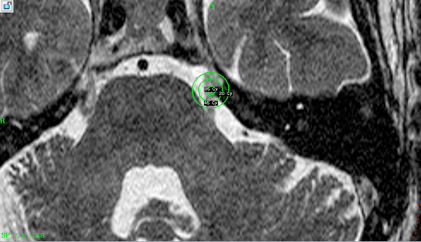

Рис 1 Мишень радиохирургического воздействия – корешок тройничного нерва месте входа в ствол мозга